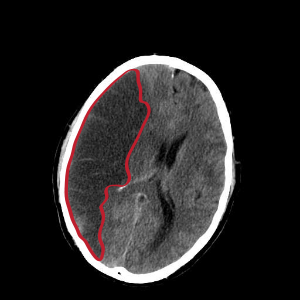

편마비, 즉 한쪽 마비란왼쪽이나 오른쪽의 상지 또는 하지 얼굴까지도 포함해서 근력저하가 일어나는 것이며 마비는 한쪽에만 생겨나는 것이 일반적이며 양 쪽 전부 이러한 증상이 나타날 경우에는 편마비라고 하지 않아요. 이러한 편마비가 오는 것은 뇌경색 전조증상이기도 하지만 해당된 질환이 다양해요. 척수종양의 경우에도 편마비가 나타날 수 있으며 디스크의 경우에도 이러한 증상이 나타날 수 있답니다.

뇌경색 초기증상 사지마비

사지마비는 양쪽 팔과 다리를 움직이기 힘들거나 전혀 움직일 수 없는 상태를 말해요. 뇌경색초기증상으로 편마비가 올 수 있는 부분도 있지만 사지마비 또한 동반해요. 사지마비는 척수신경 손상으로부터 비롯되며 목부터 허리까지 이어져 있는 경우 척추뼈에는 척수라는 신경이 있어요. 이 척수신경이 손상을 받을 경우에는 사지마비가 오게 돼요. 이렇게 사지마비가 오는 경우도 뇌경색 전조증상으로 볼 수 있어요.